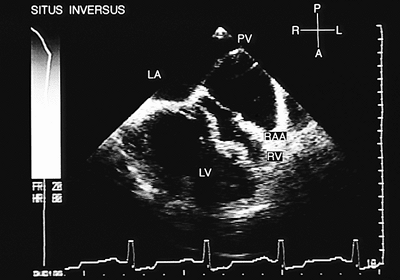

Situs Inversus

In situs inversus, the right-sided appendage has the characteristics of an anatomically left appendage (Fig. 8.2.7), whereas the left-sided appendage has the characteristics of an anatomically right appendage (Fig. 8.2.8). The atrial cavity on the right is connected to the pulmonary veins (Fig. 8.2.9), whereas the atrial cavity on the left is connected to the venae cavae and receives the coronary sinus. When contrast studies are performed, the atrial chamber situated on the left is opacified (Fig. 8.2.10). The eustachian valve can be recognized in the atrium situated on the left (Fig. 8.2.11). The connection of the suprahepatic veins to the inferior vena cava and its drainage into the atrium situated on the left can be observed in transgastric recordings (Fig. 8.2.12).

When situs inversus is present, the A–V discordance is demonstrated on observing that the left atrium situated on the right is connected to the anatomically right ventricle situated on the right, and the right atrium situated on the left is connected to the anatomically left ventricle situated on the left (Fig. 8.2.28).